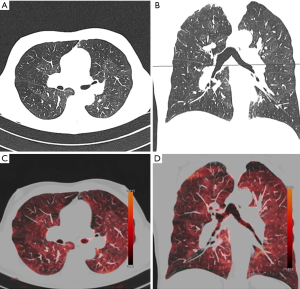

Conventional dual energy CT

Another technique for quantification of emphysema is based on dual-energy CT (DECT) (Figure 4). With this technique pulmonary perfusion is assessed by the measurement of iodine dispersion maps or lung ventilation by measurement of the distribution of injected iodine contrast media (39). The principle the technique is the acquisition of images at different X-ray energies in order to analyse the resultant images for differences in attenuation. With this approach iodine maps of the lung parenchyma reflecting the perfusion can be generated. These maps can provide additional physiological information in patients with lung emphysema as mere morphological assessment with standard CT can (40). Pansini et al. (41) evaluated pulmonary perfusion on a lobar level in tobacco users with dual-energy CT to investigate for connections between the degree of parenchymal destruction and alteration of pulmonary perfusion. They found that regional alterations of pulmonary perfusion can be visualized by dual-energy CT in smokers with predominant emphysematous lung changes.

Lung perfusion scintigraphy has been traditionally used to assess potential candidates for LVR surgery with severe emphysema. Despite this method can assess the perfusion pattern in patients with severe emphysematous changes, it suffers from low spatial resolution. MRI seems to be a more promising technique, since it has shown to have high diagnostic accuracy in the detection of perfusion abnormalities and the ability to provide lobar and segmental assessment of perfusion defects (42,43). Yet, none of the afore mentioned methods is able to evaluate morphological changes of the lung parenchyma, such as thin-collimated high-resolution CT can. Hence, full assessment of lung destruction and impaired lung function require a combination of morphological and functional information or creation of fusion images using an additional technique. This is in contrast to dual-energy CT:

The technique can be used as a one-stop-shop tool, which is able to combine the functional information of scintigraphy/MRI with the superior structural information of CT.